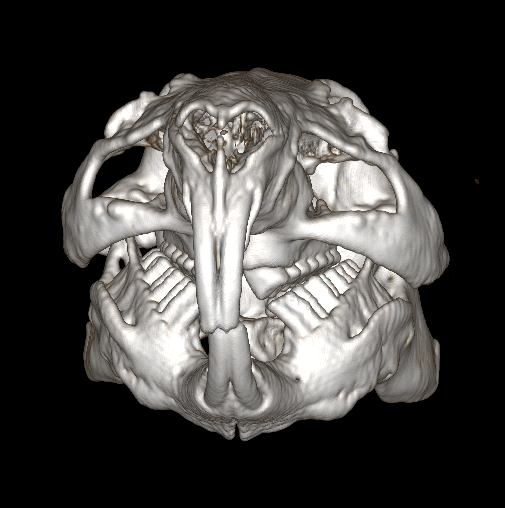

Guinea pig dentition

Guinea pigs have continuously growing teeth, just like rabbits, but the dental formula, shape and orientation of the teeth are quite different to rabbits. read more

Dental procedures in rabbits and guinea pigs

British Veterinary Zoological Society, in collaboration with the Rabbit Welfare Association & Fund, recently released a position statement on the use of anaesthesia in rabbit and guinea pig dental procedures. read more